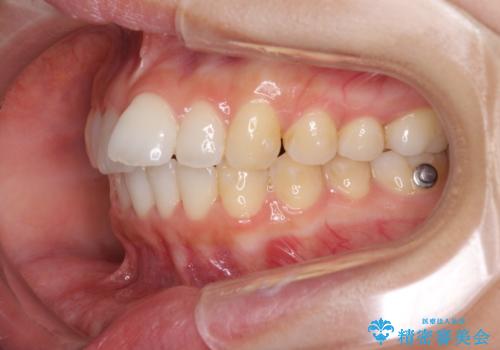

- 1本飛び出した前歯を治したいとのことで来院された患者様です。

歯列全体の拡大とIPR(歯と歯の間を削る)によってデコボコが解消するようにし、さらにゴムかけを活用して右側の咬み合わせ位置を変えるように設計し、インビザラインにより治療を行うこととしました。

後方移動に際し、上下顎の親知らずは3本とも抜歯することとしました。

結婚式までに前歯を整えたいとのことでしたが、インビザラインでは先に奥歯を移動させてから前歯を動かすため、間に合わない可能性がありました。しかし、結婚式までに期間があったことと、マウスピースをしっかりと装着してくださったことで、十分な歯列に整えることができました。